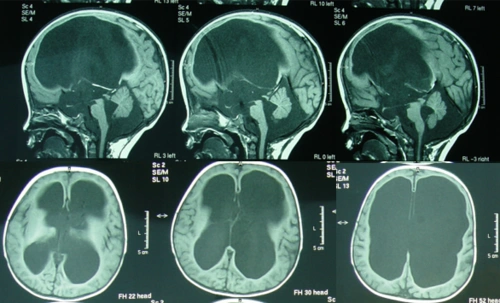

手把手教你基础颅脑mr平扫及后处理

超实用急诊头颅ct3b阅片法

读懂头颅ct并不难教你成为读片小能手

图-:2010年9月7日头颅ct整合.png

头颅ct解剖与常见出血梗死判读